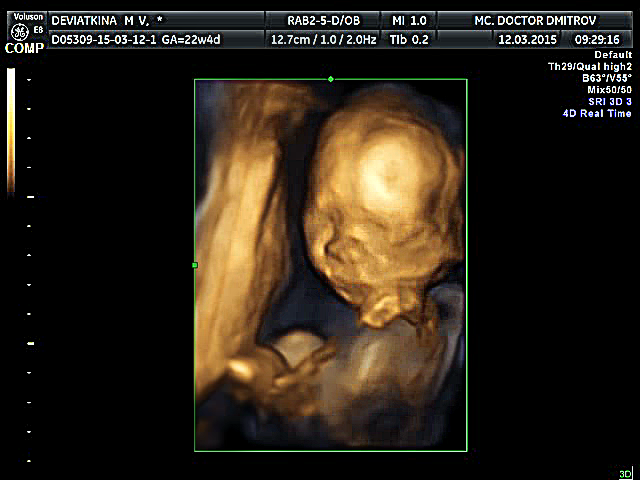

Посмотрите на наше чудо:

Нам уже 22 недельки и 4 дня. Вес нашего второго котика уже почти 500гр. Узистка сказала что крупный уже мальчик и длинненький. ИИИИИ ухи лапоухи )))))